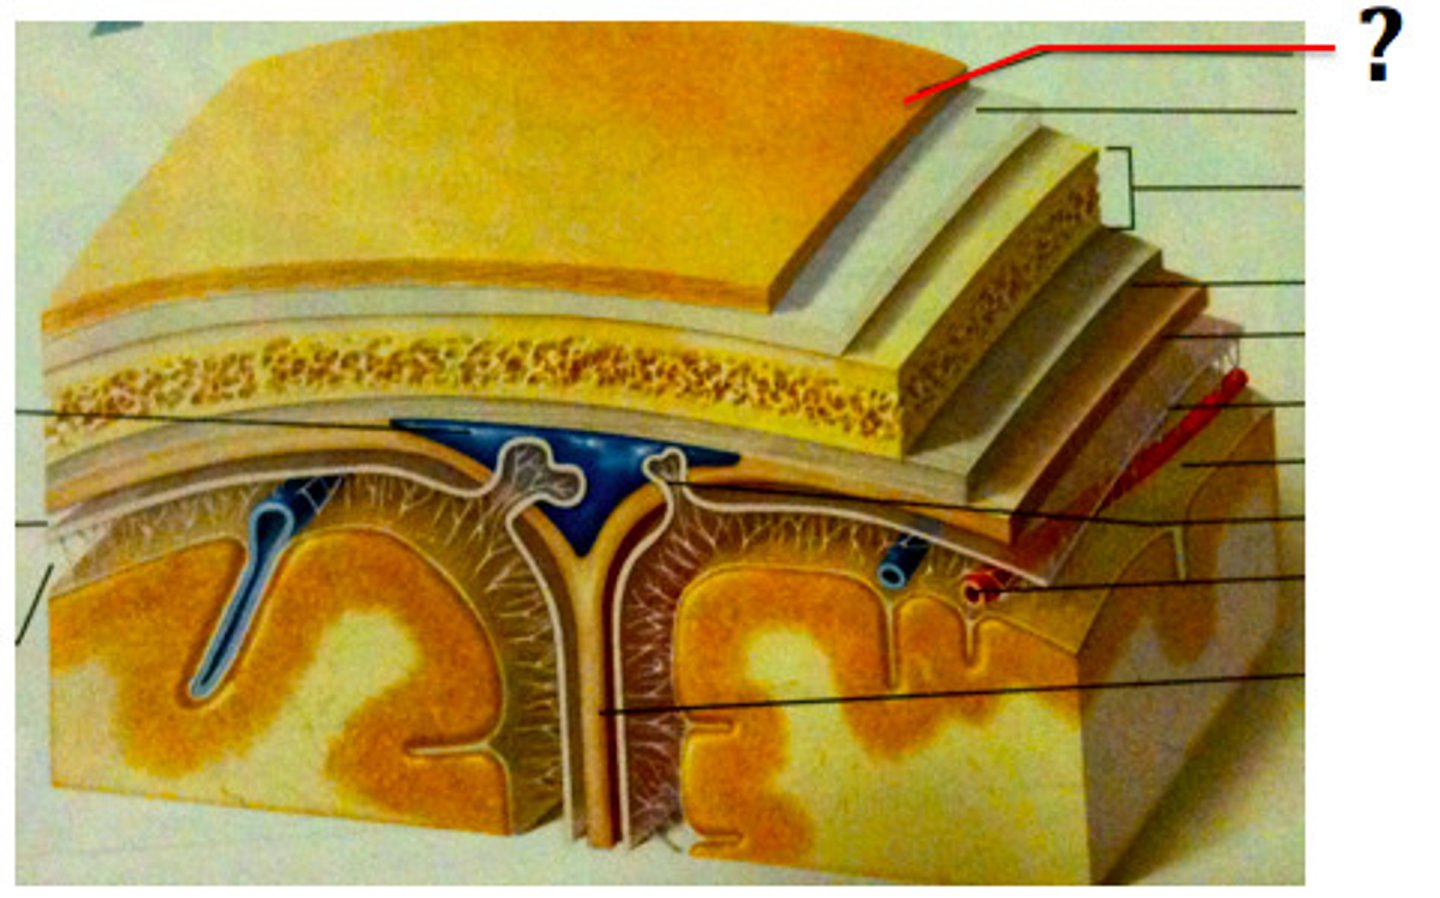

2 important anatomical structures that protect the brain

cranium & meninges

cranium

bony part of brain

meninges

fibrous tissue

3 layers make up the meninges

dura mater, arachnoid mater, pia mater

dura mater

outer periosteal layer & inner meninges layer

periosteal and meningeal

two layers of dura mater